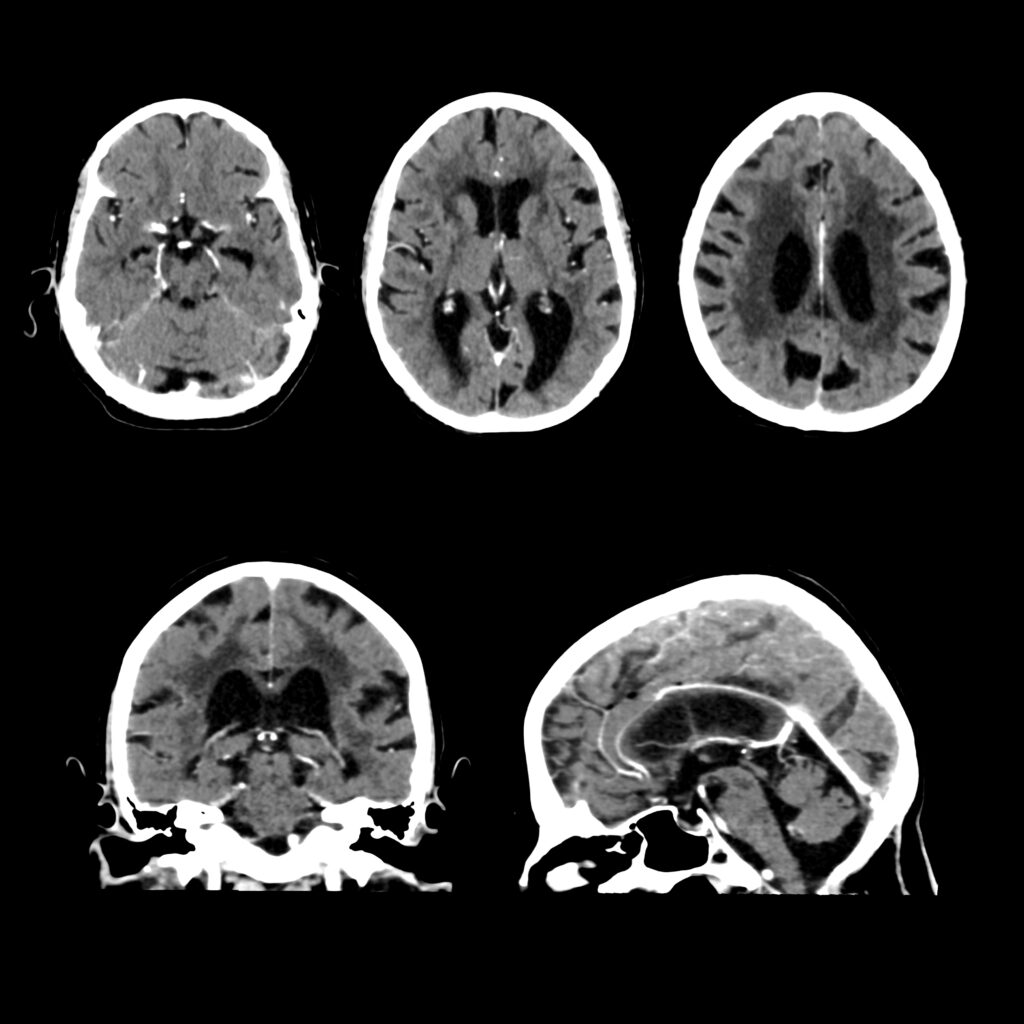

CT SCAN

img01

CT-Scan Aquilion Prime SP

• Comfortable & Fast Experience

Wide 78 cm open design and extremely fast scanning reduce stress, breath-holding, and discomfort — perfect for children, elderly, and nervous patients.

• Low Radiation for Your Safety

Advanced dose-reduction technology keeps radiation as low as possible while still delivering clear, reliable images.

• Clear & Accurate Results

High-resolution, 160-slice imaging provides sharp detail for chest, abdomen, brain, spine, blood vessels all angiographic studies (Coronary Angio) CALCIUM SCORE, full-body assessments and stroke evaluation.

• Ideal for All Patients

Comfortable for larger or mobility-impaired patients thanks to the wide opening and quick exam times.

• Great for Emergency & Routine Scans

Captures fast, precise images for trauma.

• Smooth, Quick Visit

High-speed imaging means less time on the table and faster results for your doctor.

• Vitrea post processing AI software

Multi-planer reformatting (MPR), 3D and 4D Advanced visualization, Quantitative analysis and measurement tools (Calcium score), Reduce noise and artifact.